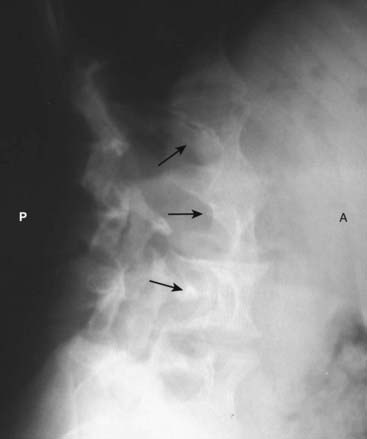

Figure 12-11 Scalloping of the vertebral bodies in neurofibromatosis.

Neurofibromatosis is a neurocutaneous disorder associated with a skeletal dysplasia. There may be numerous skeletal abnormalities associated with the disease, including scalloping of posterior vertebral bodies (solid black arrows), especially in the thoracic or lumbar spine (as shown here). This is produced by diverticula of the thecal sac caused by dysplasia of the meninges that leads to erosion of adjacent bone through the pulsations transmitted via the spinal fluid. (A is anterior and P is posterior.)

image Neurofibromas can occur as an isolated tumor arising from the Schwann cell of the nerve sheath or as part of a syndrome called neurofibromatosis. As part of the latter, they are a component of a neurocutaneous bone dysplasia that can cause numerous abnormalities, including subcutaneous nodules, erosion of adjacent bone (rib notching), scalloping of the posterior aspect of the vertebral bodies (Fig. 12-11), absence of the sphenoid wings, pseudarthroses, and sharp-angled kyphoscoliosis at the thoracolumbar junction.